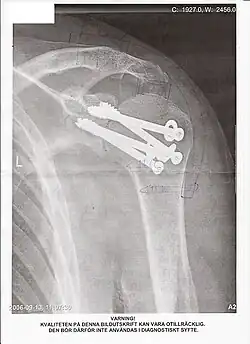

Das Verfahren der offenen Arthrodese sieht eine Resektion der knorpeligen Anteile des Gelenks vor, oft mit Entfernung des darunterliegenden Knochens, wodurch auch eine Achskorrektur erreicht werden kann. Anschließend erfolgt in der Regel eine interne Fixation mit einer Osteosynthese. Dabei können kanülierte (hohle) Schrauben (wie im Bild der Schulter-Arthrodese), K-Drähte, intramedulläre Nägel oder Platten angewandt werden. Dies hängt von der Lokalisation der Arthrodese, der Präferenz des Operateurs und der speziellen Indikation ab. Zur Verbesserung der Knochenheilung können zudem ein eigenes Knochentransplantat (Beckenkamm-Spongiosa) oder künstliche Knochenersatzmaterialien angelagert werden. Nach der Operation ist in der Regel eine mehrwöchige Ruhigstellung in einem Gipsverband oder Schiene nötig, damit eine knöcherne Durchbauung des ehemaligen Gelenkes stattfindet.